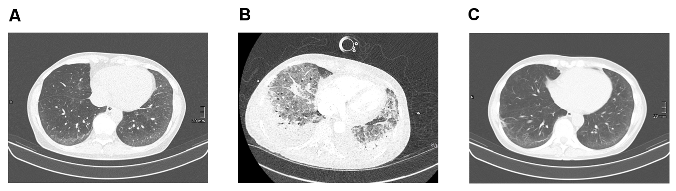

Abbildung 1: 1A: Thorax-CT bei Diagnosestellung SSc-ILD, 1B: Thorax-CT bei ARDS, 1C: Thorax-CT am Ende der Ganciclovir-Therapie

Vorgeschichte: Bei einer 60-jährigen Patientin wurde im Juli 2024 die Diagnose einer systemischen Sklerose (klinisch limitiert, ANA/anti-Scl70-AK pos.) mit initialer pulmonaler Manifestation (NSIP-Muster) gestellt, und eine Immunsuppression mit MMF 2x1.000 mg eingeleitet (Abbildung 1A [Fig. 1]).

Diagnostik und Verlauf: Laborchemisch bestand eine systemische Inflammation (CRP-Wert initial 36 mg/l) bei normwertigem PCT-Wert. Im Routinelabor war ein deutlich erhöhter LDH-Wert auffällig (506 IU/l). Im CT-Thorax fand sich eine deutl. Zunahme der interstitiellen Lungenveränderungen mit neuer Milchglaskomponente. Neben einem Progress der SSc-ILD wurde insbesondere auch an eine infektiöse Genese der Lungenveränderungen gedacht. Die MMF-Therapie wurde beendet und eine umfangreiche mikrobiologische Diagnostik veranlasst. In PCR-Analysen des Rachenspülwassers fand sich ein schwach positiver Befund für CMV-DNA (6,2 x102 Kopien/ml) bei unauffälligen Befunden für Pneumocystis, HSV1/2, Influenza A/B, Parainfluenza I-III, RSV, HMPV und Adenovirus. Es wurde eine Therapie mit Ganciclovir i.v. initiiert sowie bei klinischer und laborchemischer Verschlechterung (Anstieg von CRP auf 176 mg/l, PCT auf 1,6 ng/ml und LDH auf 909 IU/l) eine rasche Bronchoskopie mit BAL durchgeführt. In der BAL konnte eine deutlich höhere Kopienanzahl von CMV-DNA nachgewiesen werden (8x104), die weiteren Multiplex-Analysen bzw. Kulturen auf resp. Erreger blieben vollständig negativ. Weitere PCR-Analysen zeigten auch positive Befunde für CMV-DNA im Blut (9,9x105 Kopien/ml) und Stuhl (3,2x102 Kopien/ml). Die CMV-Serologie ergab positive Titer für CMV-spezifische IgM- und IgG-AK, wobei für die IgG-AK nur eine sehr geringe Avidität gemessen wurde (2,9%). Trotz der Ganciclovirtherapie entwickelte die Pat. ein ARDS und musste intensivmedizinisch versorgt werden (Abbildung 1B [Fig. 1]). Unter einer fortgesetzten Ganciclovirtherapie, invasiven Beatmung und Bauchlagerung gelang eine Stabilisierung und im Verlauf Besserung der resp. Situation. Konsekutive PCR-Analysen zeigten abfallende und im Verlauf negative Befunde für CMV-DNA in der BAL, im Blut und im Stuhl. Wiederholte Serologien zeigten einen Anstieg der Avidität der CMV-spezifischen IgG-AK bis auf 35,1%. In einem Verlaufs-CT konnte eine vollständige Rückbildung der akut entzündlichen Lungenveränderungen bei unveränderten Befunden der SSc-ILD dokumentiert werden (Abbildung 1C [Fig. 1]). Die im Verlauf auf orales Valganciclovir umgestellte Therapie konnte deshalb 01/2025 beendet und bei weiterhin stabilem Verlauf die Immunsuppression mit MMF 03/2025 bei SSc-ILD wieder aufgenommen werden. Nach einer Rehabilitationsmassnahme kann sich die Patientin inzwischen wieder intensiv sportlich betätigen (Skitourengehen).